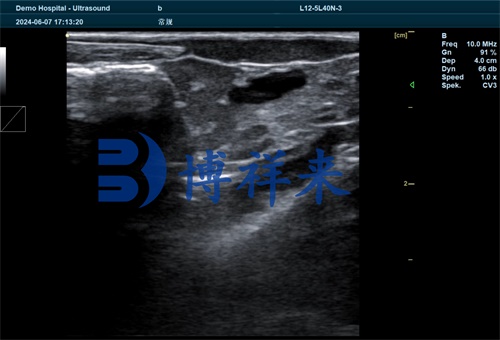

One notable application of fish ultrasound is in monitoring muscle and fat ratios, which are critical indicators for market readiness. Fat content directly impacts flavor, shelf life, and processing quality. With a high-resolution ultrasound probe, it is possible to visualize subcutaneous fat layers and deeper musculature in real time. Farmers can thereby optimize feeding strategies and harvest schedules based on actual body composition rather than estimation. This has direct implications for economic efficiency and product quality.

Of course, selecting the right ultrasound model for fish applications is critical. Portable, waterproof, and high-resolution systems are best suited for aquatic environments. The probe should be capable of shallow-depth imaging with sufficient sensitivity to detect soft tissues in fish of varying sizes. A convex or microconvex rectal probe is often ideal for scanning through the fish's ventral surface, especially for gonadal observation.